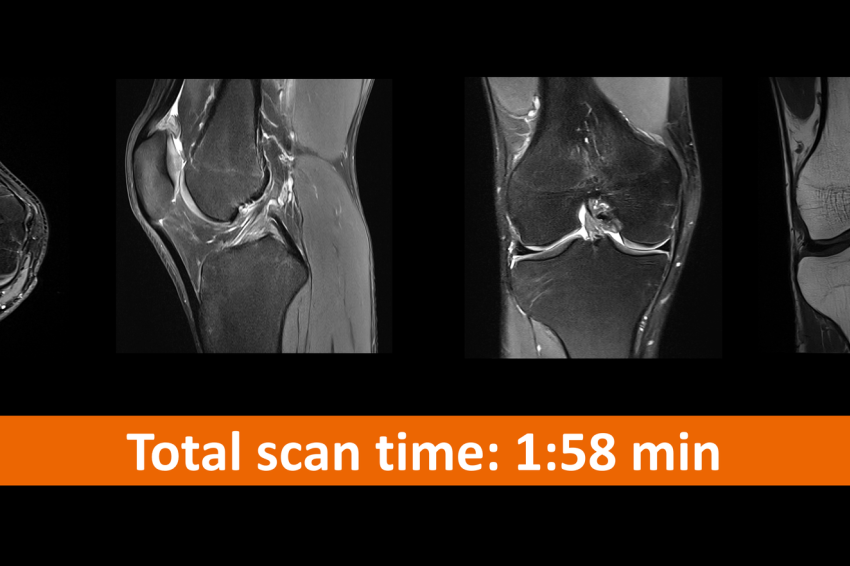

Remenix Crizantemelor este una din unităţile medicale din România folosesc echipamente şi tehnologii de ultimă generaţie, precum tehnologiile Deep Resolve în cazul rezonanţei magnetice, prin care se obţin imagini de înaltă calitate în timp extrem de scurt cu ajutorul inteligenţei artificiale. Inainte, imaginile de mare rezoluţie se puteau obţine numai cu un timp lung de scanare, în timp ce o examinare rapidă însemna renunţarea la o bună rezoluţie spaţială a imaginii. Acum, tehnica Deep Resolve, compusă din mai multe opţiuni – Deep Resolve Gain, Deep Resolve Sharp, Deep Resolve Boost şi Deep Resolve Swift Brain – fac ca timpul de scanare să fie extrem de mic, cu beneficiu major pentru pacient, care nu trebuie să rămină mult în RMN și care implică un disconfort, păstrând o rezoluţie crescută a imaginii, ceea ce se traduce prin posibilitatea unui diganostic de certitudine, evidenţiind patologii care poate până acum nu erau vizibile sau erau greu de pus în evidenţă. Un plus la noul sediu, Remenix Crizantemelor este ca beneficiati de cele mai noi echipamente medicale imagistice de RMN si CT din regiune Galați- Brăila (fabricate în Germania 2023) dar regăsiți și singurul aparat de rezonantă magnetică cu diametru magnet de 70 cm, perfect pentru pacientii cu frică de spații închise, claustrofobi, sau supraponderali și capabil scanare whole body (tot corpul) într-un timp foarte scurt!